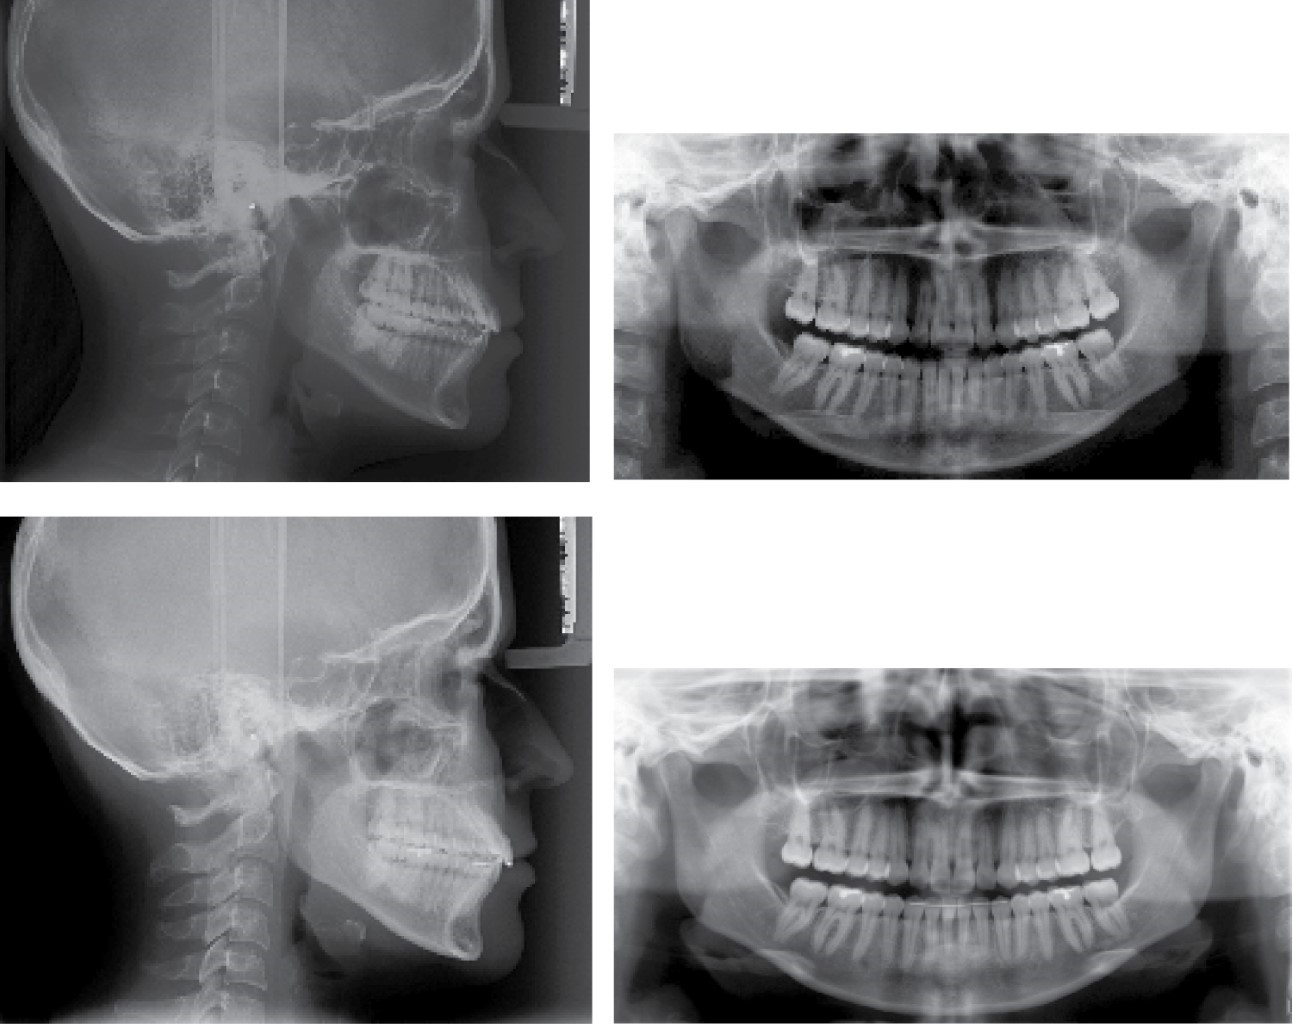

Paciente femenino de 24 años que acude a Clínica de Ortodoncia en la Escuela Nacional de Estudios Superiores Unidad León para corregir un canteamiento evidente. No presenta enfermedades crónicas ni datos patológicos que interfieran con el tratamiento. Diagnóstico: clase I esquelético biprotrusiva con crecimiento neutro, facialmente es una paciente braquifacial con perfil recto y retroquelia, se observó asimetría facial en la comparación del lado izquierdo y derecho. Incisivos superiores proinclinados, giroversiones, clase molar III derecha e izquierda, clase I canina bilateral, línea media desviada y plano maxilar canteado donde se observa que se necesita una intrusión de 5 mm para corregirlo (Figuras 1, 2 y 3).

Fase 3: mecánica principal, arco 0.019" × 0.025" SS superior y 0.016" × 0.025" SS inferior (Figura 4).

Fase 4: final, arcos TMA 0.019" × 0.025" superior y 0.016" CuNiTi inferior y elásticos de asentamiento superior e inferior. Retención: fijo superior e inferior.

Los resultados a los tres meses de revisión fueron satisfactorios, se observa una intrusión evidente, resultados de la biomecánica tal como la mordida abierta posterior, que se fue solucionando con diferentes métodos y teniendo control de torque en todo momento (Figuras 5, 6, 7 y 8).

Figura 6

Figura 7

Figura 8